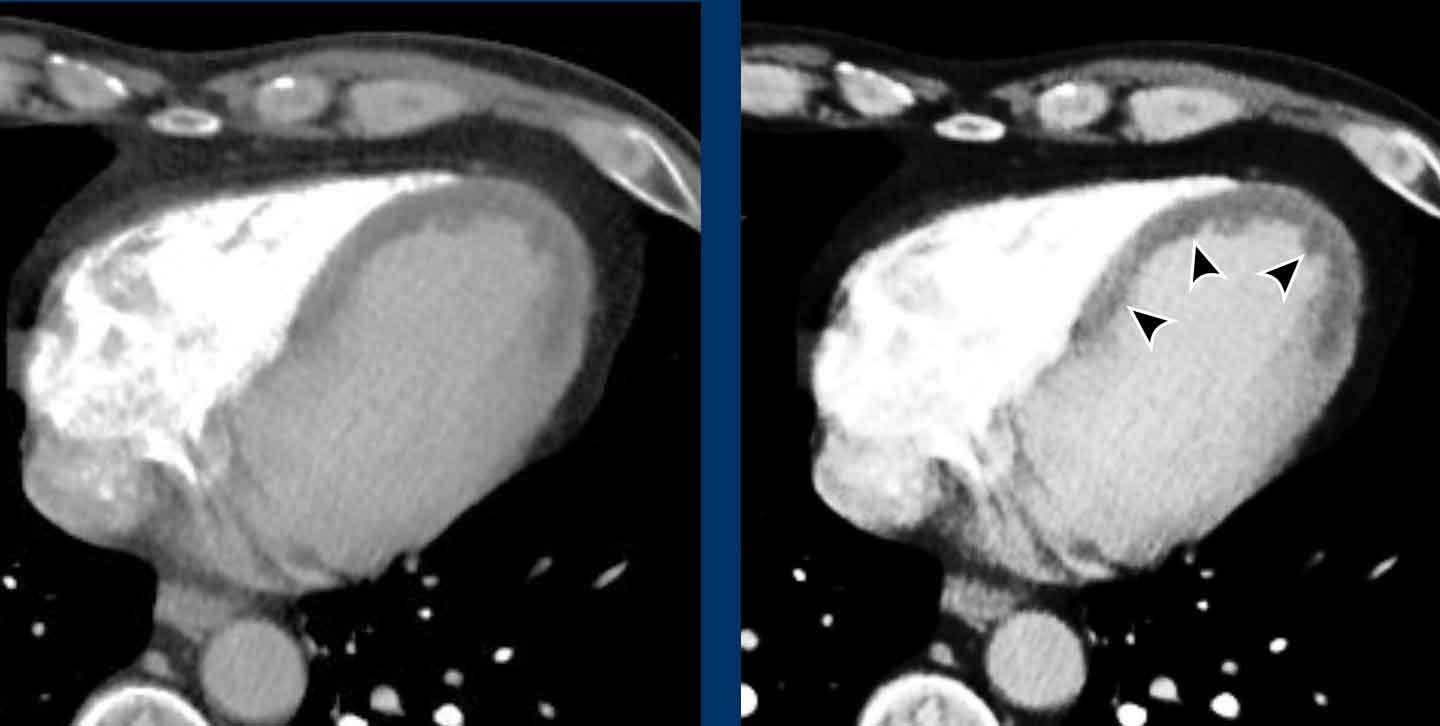

Hình ảnh

Nhĩ trái giãn.

Có huyết khối trong tiểu nhĩ trái (mũi tên) lan rộng về phía nhĩ trái (đầu mũi tên).

Tại tiểu nhĩ trái, thường gặp khó khăn trong chẩn đoán phân biệt hình ảnh giữa huyết khối và hiện tượng ngấm thuốc không hoàn toàn do dòng chảy chậm, đặc biệt khi chụp ở thì thuốc sớm.

Vấn đề này có thể được giải quyết bằng cách chụp CT ở thì thuốc muộn hơn hoặc chụp ở tư thế nằm sấp.

Siêu âm tim qua thực quản được coi là tiêu chuẩn vàng.